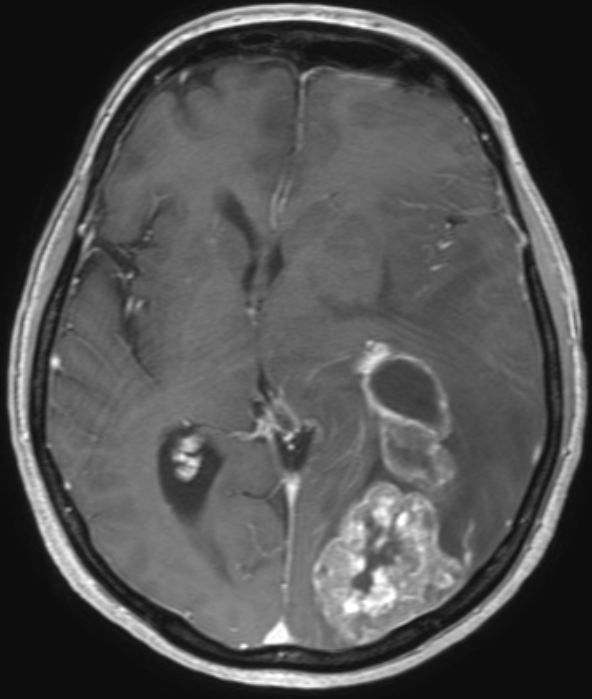

| Hirnmetastase | 48-jährige Frau, die vor 4 Jahren ein DLBCL Stadium IVa mit Bulk rechts inguinal, Lymphknoten mediastinal axillär links, Milzvergrößerung und pulmonale Infiltration hatte. 8mal R-CHOP, RT der rechts inguinalen Lymphknoten mit 26 Gy. Vor 5 Monaten Tumor linker Hilus und Hirnmetastase links occipito-parietal: Histologie: großzelliger neuroendokriner Tumor. Entfernung der Hirnmetastase, RT Neurocranium. 6 x Carboplatin/Etoposid: PR des Lungentumors, vitaler Resttumor des Gehirns | |||||||||||||||||||

MRT T1 FFE: Ausgedehnte Matastase li occipital.![]()  | |||||||||||||||||||